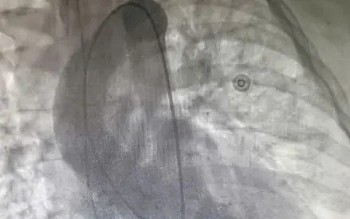

Ngày 19.3, Thạc sĩ, bác sĩ chuyên khoa 1 Nguyễn Xuân Trường (Trung tâm Chấn thương chỉnh hình, Bệnh viện đa khoa Tâm Anh TP.HCM) cho biết, qua kết quả chụp X-quang, các bác sĩ xác định bé bị gãy xương đùi phải, với hai đầu xương bị di lệch. Để đảm bảo quá trình phục hồi tốt nhất, các bác sĩ đã quyết định sử dụng phương pháp bó bột toàn thân, từ cổ chân đến ngực.

| Các bác sĩ tiến hành can thiệp, bó bột cho trẻ (Ảnh: BV). |

Bác sĩ Trường giải thích rằng vị trí gãy xương gần khớp háng khiến bé dễ dàng co duỗi, chuyển động toàn thân. Trong khi đó, trẻ em chưa đủ ý thức và hệ xương, cột sống chưa vững, điều này khiến việc bó bột dài là phương pháp tối ưu. Bó bột từ cổ chân đến ngực giúp tạo ra môi trường ổn định, cố định toàn bộ và hạn chế chuyển động của chân và thân, đồng thời bảo vệ tốt hơn cho khớp háng và xương sống trong quá trình hồi phục.

Quá trình gây mê gặp nhiều khó khăn do tĩnh mạch ở tay bé quá nhỏ, buộc bác sĩ phải tiêm vào vùng bẹn, nơi có nhiều mạch máu và dây thần kinh. Bé sợ hãi và không thể giữ tư thế ổn định, vì vậy bác sĩ phải thao tác hết sức thận trọng. Sau hơn một giờ, việc bó bột toàn thân được hoàn tất. Kết quả can thiệp được đánh giá là thành công, giúp cố định phần xương gãy, tạo điều kiện cho xương hồi phục nhanh chóng, đồng thời giảm nguy cơ nhiễm trùng hoặc biến chứng nếu bột bị lỏng lẻo.